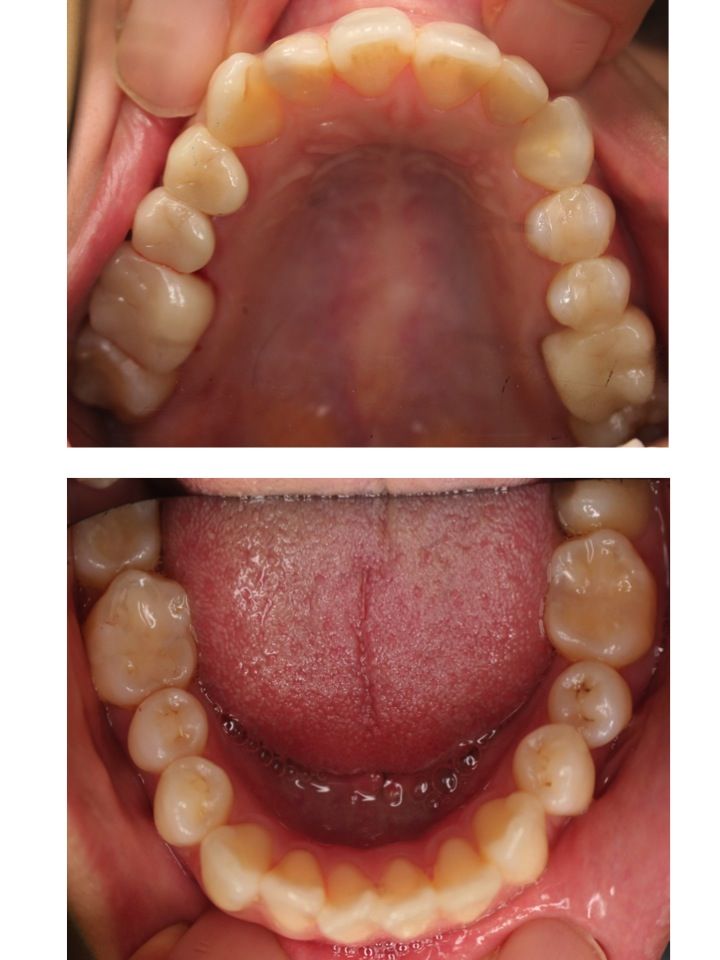

以下は、治療後の上下顎の写真です。